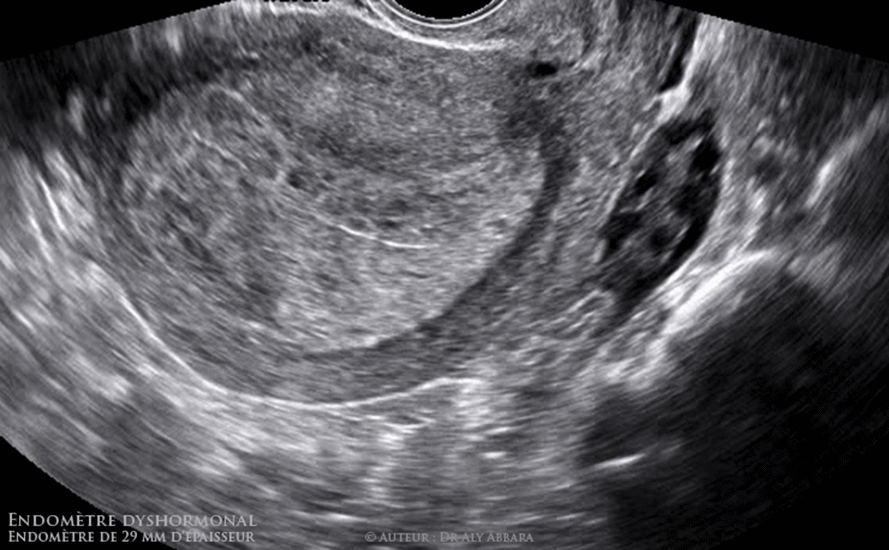

Utérus : endomètre dyshormonal de 29 mm d'épaisseur ; il s'agit d'un épaississement asymétrique : endomètre postérieur = 18 mm / endomètre antérieur = 11 mm.

• L’hystéroscopie exploratrice montre qu'il s'agit d'un important épaississement prédominant au niveau de l'endomètre postérieur qui prend un aspect polypoïde et cérébroïde.